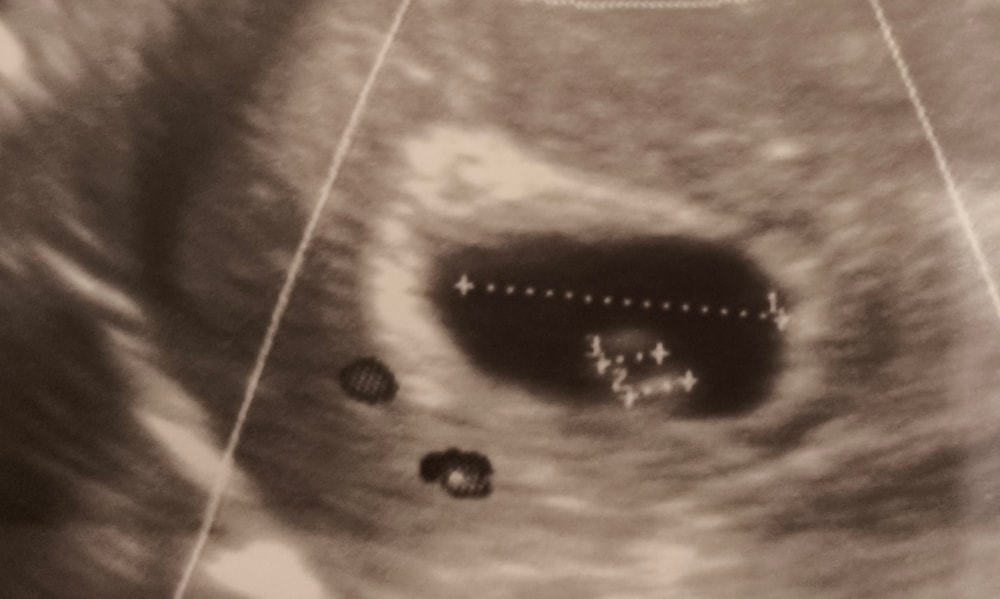

23 дпп. первое узи. креветка на базе

Я официально беременна, на узи 6 недель, эмбрион, сердцебиение (замерить не смогли, маленький). Продолжаю ничего не чувствовать, единственное, значительно притупился аппетит, я думаю, это лайт токсикоз.